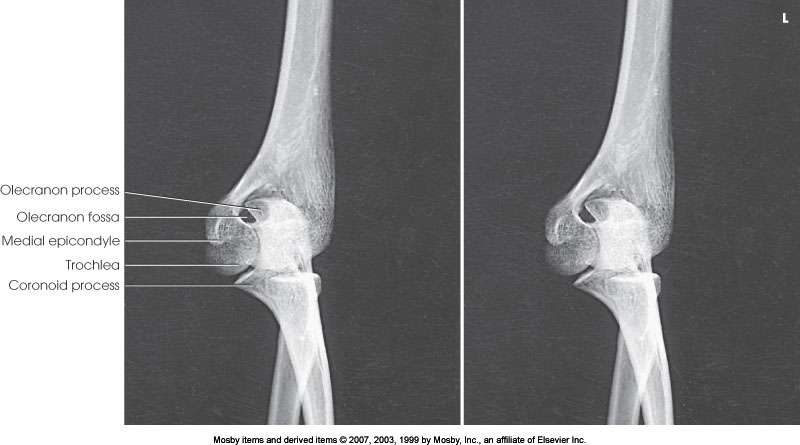

What position is demonstrated?

Lateral Elbow